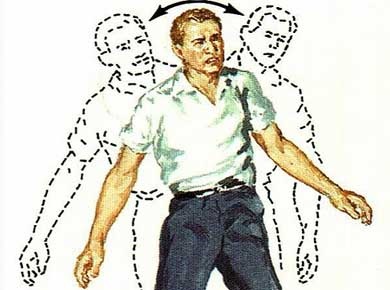

Când leykoareoz 1 grad la pacienți, de asemenea, pot prezenta o coordonare ușoară afectarea mișcărilor: o lungime pas și reducerea vitezei de mers.

La trecerea în patologia etapa a 2-a manifestărilor clinice leucoaraioză devin mai pronunțate. Prin caracteristicile menționate mai sus sunt adăugate la o deteriorare puternică în memorie și de concentrare, tulburări ale funcției motorii, mai vie (mișcare haotică).

leucoaraioză gradul III caracterizat prin extinderea considerabilă a zonelor afectate ale creierului, ceea ce duce la aprofundarea tuturor semnelor clinice ale bolii. Astfel de pacienți nu pot duce o viață plină, care are nevoie de monitorizarea și susținerea celor dragi constante.

Acesta ia act de tulburare de coordonare puternică până la pierderea echilibrului de albastru urinării, arbitrară, inhibarea puternică a funcțiilor psihomotorii, etc.